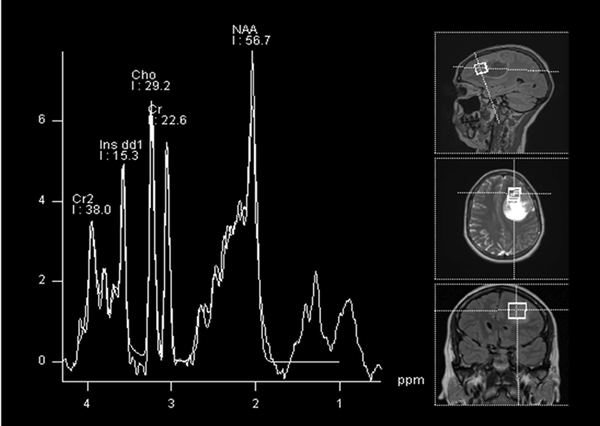

En la RM de columna cérvico-dorsolumbosacra no se observaron lesiones focales. En el análisis espectroscópico sobre la lesión se reconoció reducción del pico de NAA (marcador neuronal) así como presencia de picos de lípidos (necrosis) que resuena en 0.9 y 1.3 ppm y pico de mioinositol que resuena en 3.5 ppm (Figura 2).

Figura 2. Espectroscopia. Se evidencia reducción del pico de NAA (marcador neuronal) así como presencia de picos de lípidos, colina y mioinositol.